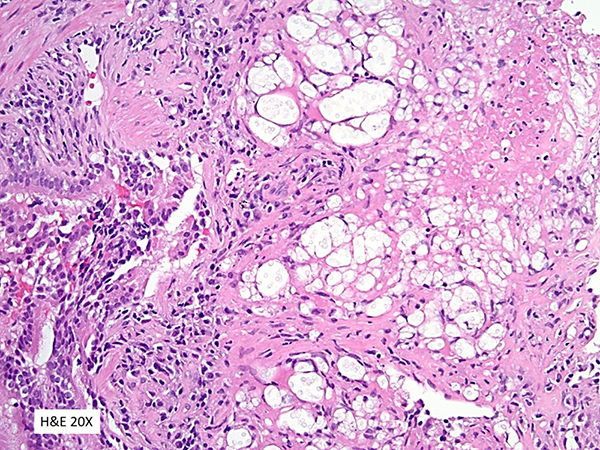

Granulomatous inflammation with focal necrosis and numerous Cryptococcus yeast.

The histologic sections in this case demonstrate the presence of granulomatous inflammation with focal necrosis and numerous pale-staining yeast forms, both in extracellular spaces and within multinucleated giant cells. A clear space (“halo”) surrounds the yeast on Hematoxylin and eosin (H&E)-stained sections. The yeast are round in shape and variable in size. Narrow-based budding is visible on H&E. Some of the yeast forms demonstrate multiple narrow-based buds. A Grocott Methenamine Silver (GMS) stain highlights the variable size of the yeast and additional narrow-based buds. Mucicarmine and Fontana-Masson stains also highlight the yeast forms.

Cryptococcus most commonly generates a granulomatous response; however, in the immunocompromised patient an inflammatory response may not be present, or the yeast forms may be associated with acute inflammation or be contained within histiocytes. Cryptococcus does not stain strongly with H&E, but is nevertheless discernible in such preparations. The cell wall is light gray. The yeast are round in shape and characteristically variable in size (6-10 microns). Budding is narrow-based and may be multiple. Evidence of a capsule may be seen as a peripheral clearing that surrounds the yeast on H&E. The GMS stain highlights the cell wall of the yeast and the characteristic variability in size. The capsule of metabolically active Cryptococcus may be highlighted by a mucicarmine stain; however, staining may be reduced due to a brisk inflammatory response or absent in a nonviable yeast. The Fontana-Masson stain highlights the presence of small amounts of melanin and melanin-like pigments present within the cell wall of the yeast, which are undetectable in H&E-stained sections. Like the mucicarmine stain, the Fontana-Masson stain may be negative in non-metabolically active yeast.